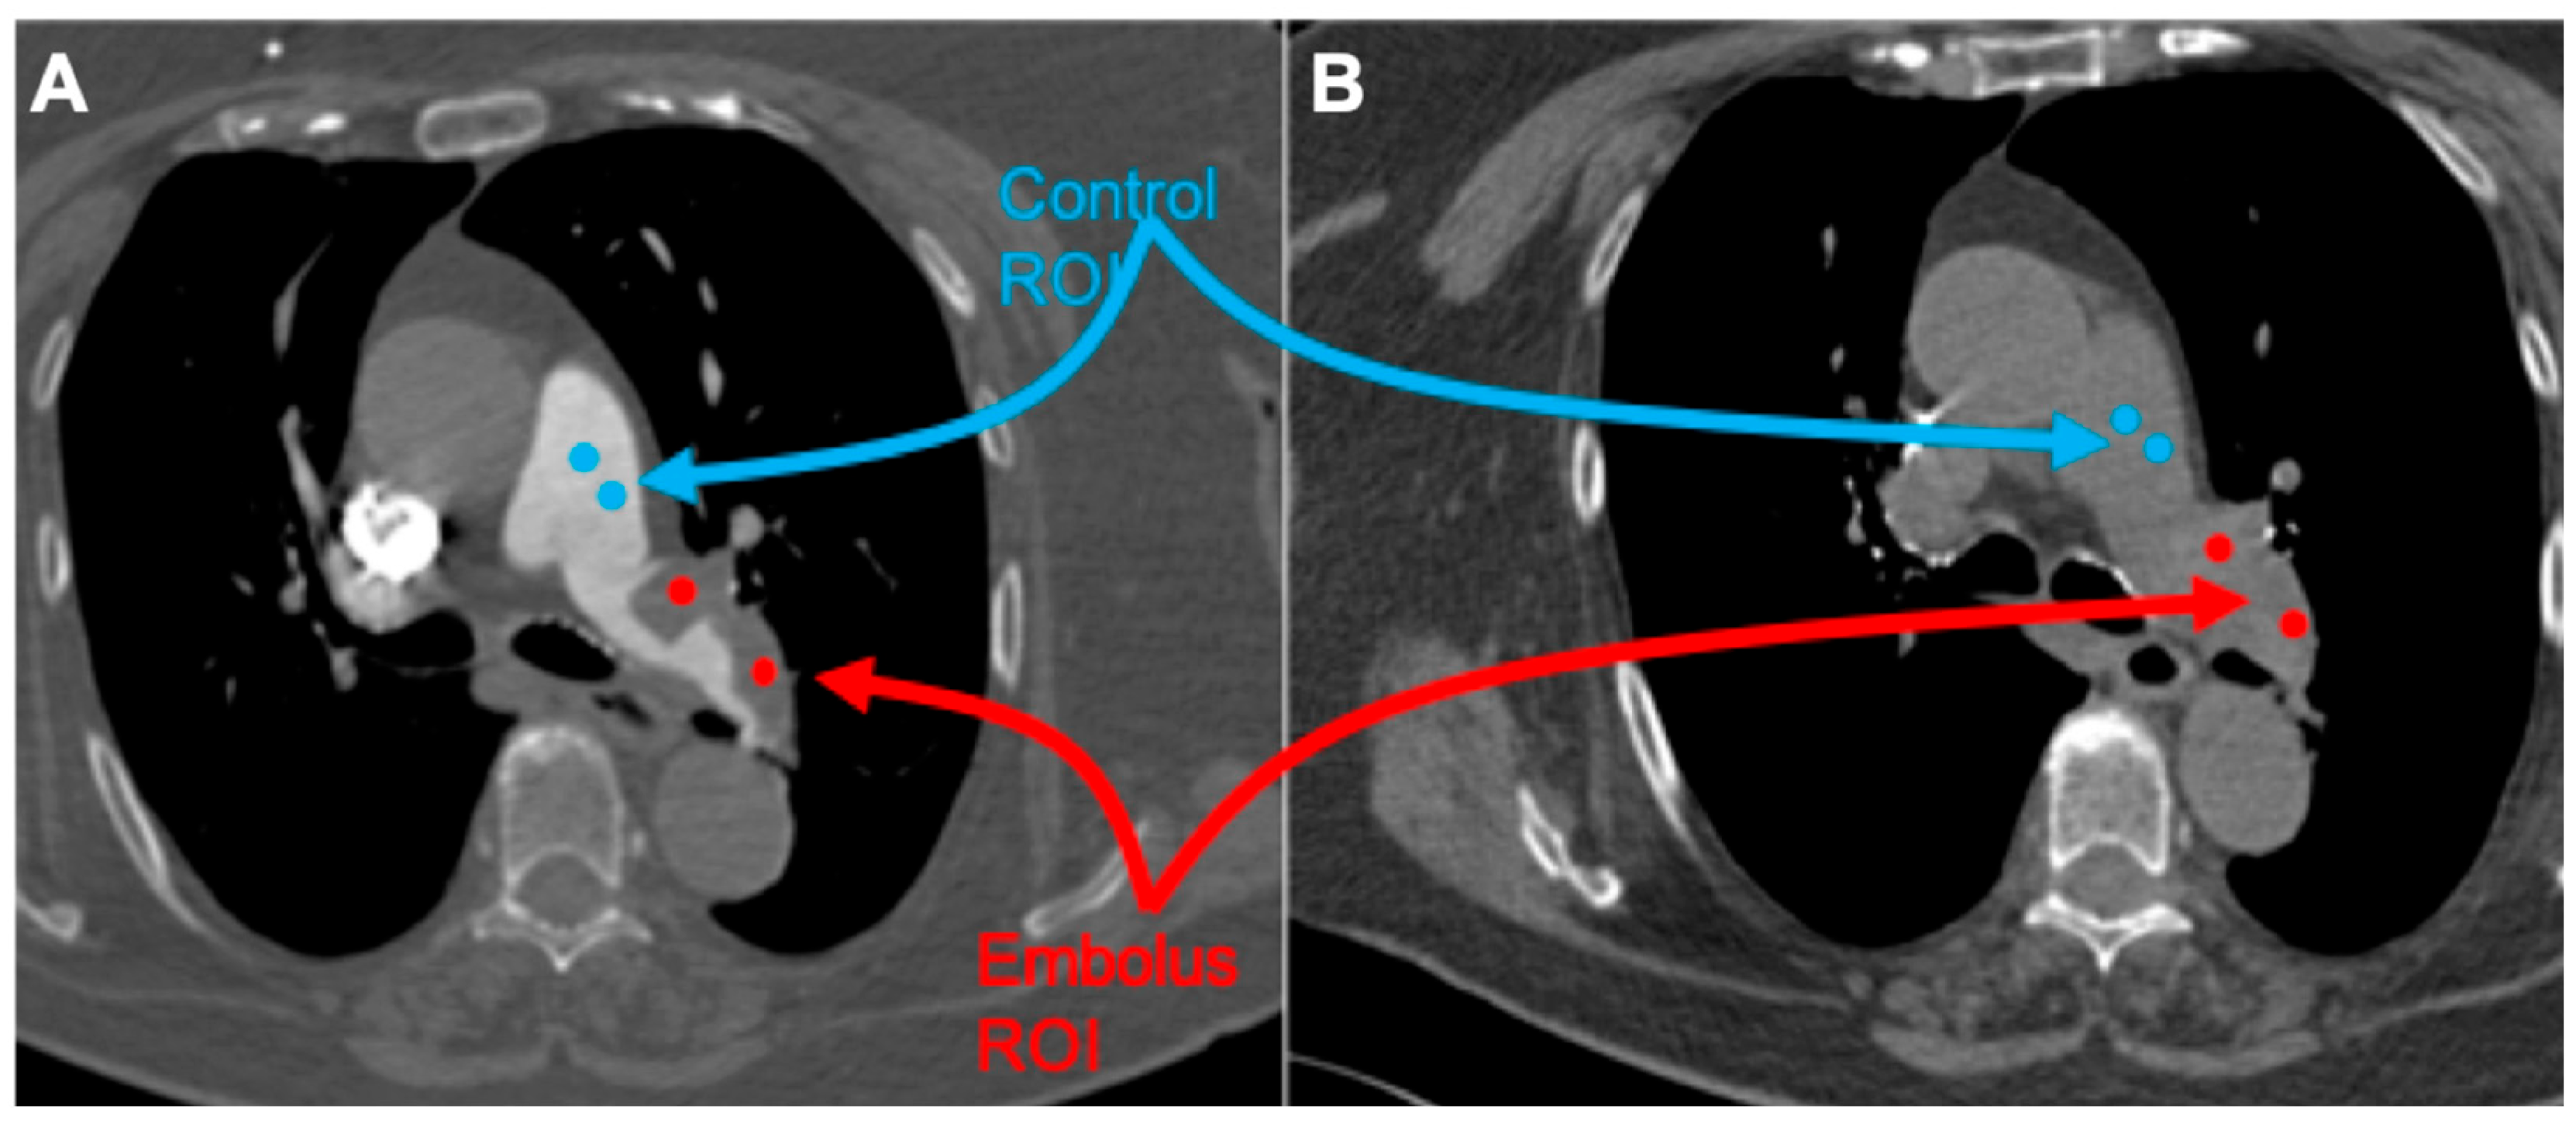

All studies were reviewed by three radiologists, with 4, 8, and more than 20 years of experience in thoracic imaging. Embolus localization was classified as pulmonary trunk, main pulmonary arteries, lobar, and segmental arteries, according to the most proximally located embolus. The emboli regions were delineated by two radiologists (with 4 and 8 years of experience in thoracic imaging, respectively) and subsequently verified by a senior radiologist (with over 20 years of experience in thoracic imaging). CT images were processed with the free available texture analysis software 3DSlicer version 4.10.2 (open-source software; https://www.slicer.org/, accessed on 1 January 2024) [18]. Couples of 5 mm diameter spherical region of interest (ROI) were placed within the largest representative slide of the pulmonary embolus and normal flow vessel as follows (Figure 1):

Figure 1. Representative case of the patient sample with acute PE with thrombus of the main left pulmonary artery. (A): Embolus (red)/control (blue) spherical ROI placed on contrast-medium-enhanced image. (B): Embolus (red)/control (blue) spherical ROI placed on the unenhanced image using the enhanced image as a reference.